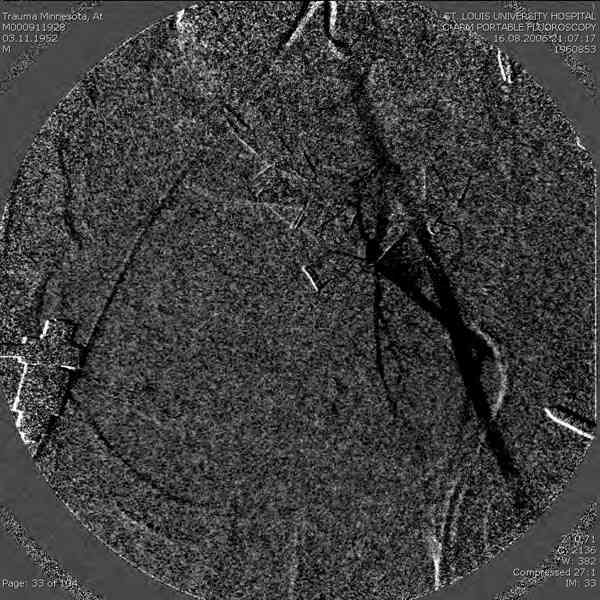

Примерно такой фиксатор наложил вчера ночью, но патология была экстренная травма: больному 53 года, поступил после мотоциклетной травмы, черепно-мозговой, абдоминальной, челюстно лицевой с потерей одного глаза, сосудистой и из скелета перелом крестца слева с диастазом симфиза и множественные переломы ребер.

Одновременно с хирургами, которые занялись ксплоративной лапаротомией, мы приступили к фиксации временным аппаратом для уменьшения диастаза симфиза. После установки аппарата удалось стабилизировать давление, потом наше место занял сосудистый хирург, который нашел кровоточащую левую артерию epigastrica. Кровоточаший сосуд затромбизировал эндоваскулярно введением 4 coil placement.

Много кровепотери было из лицевых ран. Кроме забрюшинной гематомы, крови накопилось в абдоминальной части между мышечными стенками и под кожей. Кровопотерю заместили более 20 доз препаратов крови и INR опустился изначалнего 9.5 до 1.0 в конце. Находится в реанимации, стабильный, надеемся через несколько дней займемся окончательной фиксацией переломов костей таза.